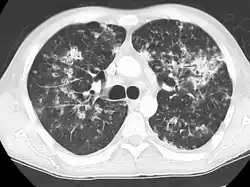

Seu nome se refere a similaridade dos seus focos de infecção com grãos de milho espalhados pelo pulmão em 90% dos exames de raio-X.

A Tuberculose miliar ou tuberculose cutânea aguda disseminada é uma classificação médica internacional para um agravamento da tuberculose por sua ampla difusão dentro do corpo humano gerando pequenas lesões na pele (de 1 a 5mm).[1]